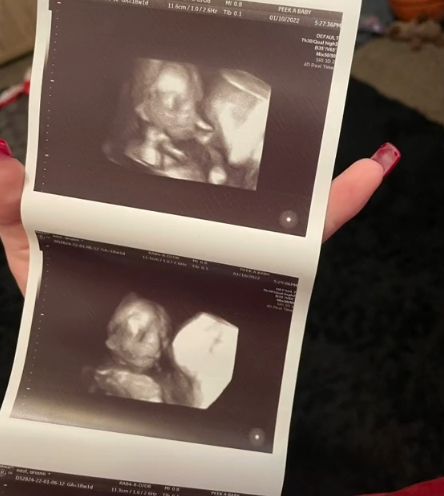

Niedawno przyszła mama wykonała pierwsze badanie USG 3D. Nie spodziewała się jednak, że na pozór niewinne badanie, wprawi ją w przerażenie.

17-tygodniowy płód ułożył się w taki sposób, jakby patrzył się wprost na sondę ultrasonograficzną. Przez to ma złowrogi wyraz twarzy, którego młoda mama kompletnie się nie spodziewała. Jak przyznaje, poczuła się niekomfortowo i początkowo bała się spojrzeć na zdjęcie.

- Moja dziewczynka wygląda strasznie, ale z dnia na dzień robi się słodsza - mówi Ariann.

Przyszła mama postanowiła podzielić się swoją reakcją z użytkownikami TikToka, którzy ją obserwują. W komentarzach przyznali, że również odbierają zdjęcie w ten sam sposób.